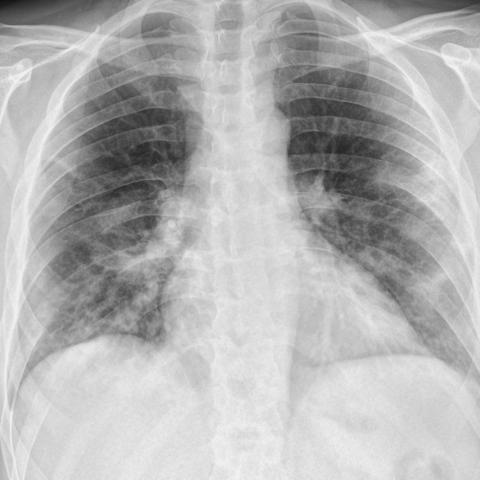

5 Experimental Results

To evaluate the performance, several metrics are considered. Accuracy score is the primary metric used for statistical classification, which is required but inadequate here as we are more interested in efficiently classifying positive samples. Thus, f1-score for the positive class is also measured. The main metric here is visualization heatmaps because the small number of positive samples make the model prone to overfitting by deciding based on the wrong features. The most common manifestations of COVID-19 pneumonia in CXRs are air-space opacities in different forms, such as GGOs or consolidations. Opacities are identified as opaque regions (whiter than usual) in CXRs. They are mostly distinguished as bilateral, involving both lungs, and multifocal opacifications. Rare findings happen in the late stages of disease course, which may include pleural effusion and pneumothorax [29].